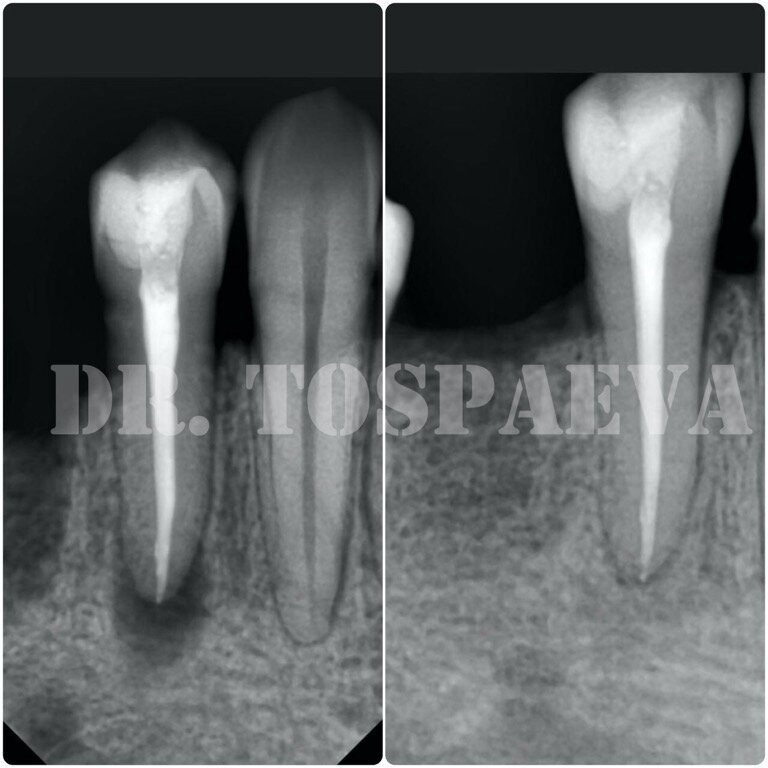

На рентгеновском снимке мы видим тёмный очаг с чёткими краями – это и есть вышеописанное воспаление («киста»).

Рентгеновский снимок того же зуба через 12 месяцев после повторного лечения. Вы можете увидеть, что участок, который ранее был тёмным пятном, значительно посветлел и в этой области появился костный рисунок.

! Нужно учитывать, что изменения за рентгеновском снимке появляются не ранее, чем через 6 месяцев! То есть судить об успехе или неудаче лечения можно по истечении полугода (если отсутствуют жалобы и зуб не болит).